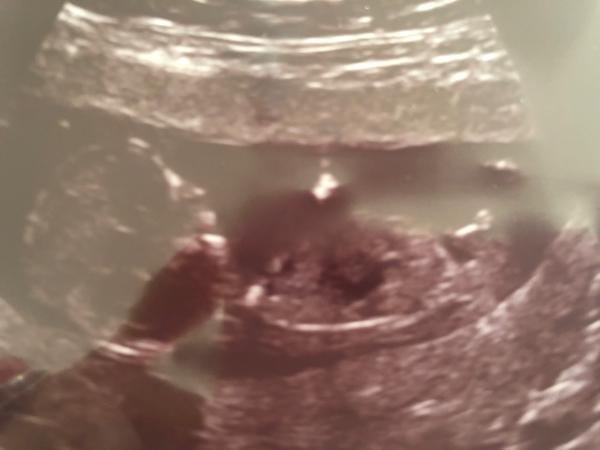

@miiiissssanek Řekla bych spíše chlapeček ♥️

@rennye anooo, pan doktor řekl také chlapečka ☺️❤️

@rennye ale mátl mě pořád ten sklon toho hrbolku 🤣 nepřišel mi ani úplně nahoru a ani úplně rovně 🤣 tak jsem si furt říkala, zda se nemohl pan doktor splést, ale myslím si, že se to už moc nestává 🤣🤣🤣

@miiiissssanek Ale stává, pořád, dokonce i na těch nejlepších ultrazvucích se může plést stín, odraz, kousek nohy apod. I na těch 4d ultrazvucích 😁